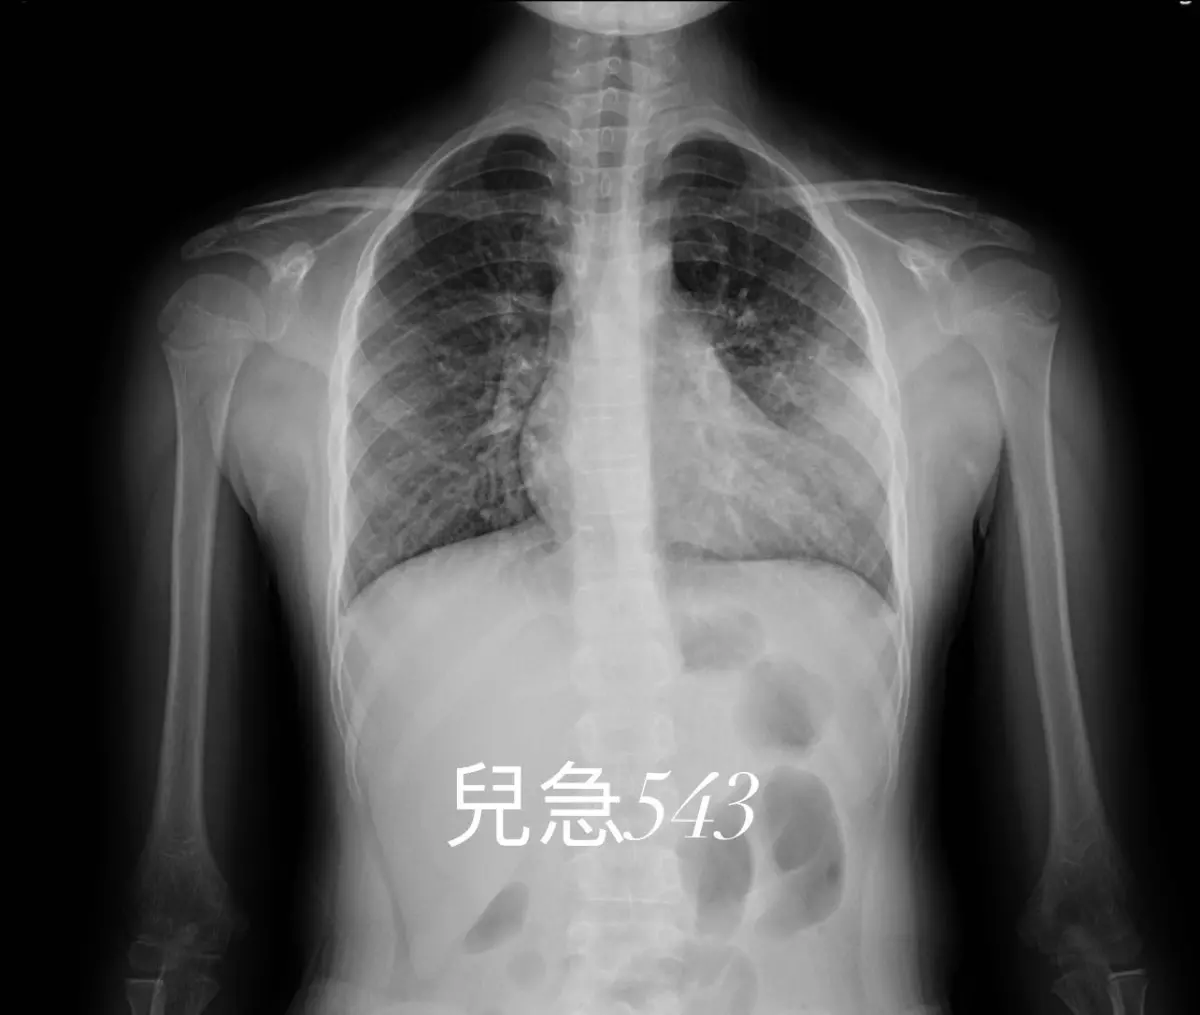

吳昌騰醫師表示,近期就曾遇到一個急診案例,有位媽媽帶來一個小女孩來急診就醫,妹妹主要問題是:「間接性發燒7天!並且有咳嗽」,這7天期間,妹妹每天有3~4次間歇性發燒,高達39.5℃。伴隨症狀包括咳嗽、咳嗽後嘔吐。媽媽曾經帶她到附近診所看了三次,也吃過藥,但是症狀還是一樣持續,最終送往急診。隨後吳昌騰醫師進行問診與抽血檢驗,發現小女孩的 CXR 顯示左下葉肺炎,並且已經有肺炎,後續抽血檢驗及PCR也證實就是肺炎黴漿菌感染導致的肺炎。